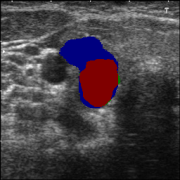

3.3 High-confidence Multi-level labels Generation

According to Reference 1 and Reference 2 discussed in Sec. 3.2, weakly supervised segmentation requires nodule location labels for location learning and region distribution labels for shape learning. In this section, we integrate geometric transformations of point annotations and segmentation from prompted MedSAM to generate high-confidence location labels for location learning in Eq. (1), as well as high-confidence foreground labels and background labels for shape learning in Eq. (2) and Eq. (3).

Specifically, as illustrated in Fig. 1, in the high-confidence labels generation phase, we derive three geometric transformations representing low-level topological information from clinical annotations:

The regions that contain high-level semantic information are generated by prompted MedSAM:

Finally, we fuse the initial topological shape ex-rectangle , in-quadrilateral , and out-rectangle and results from prompted MedSAM to generate high-confidence location , foreground , and background labels .

| (4) | ||||

where denotes the logical OR operation applied to the positions of two masks, while represents the logical AND operation.